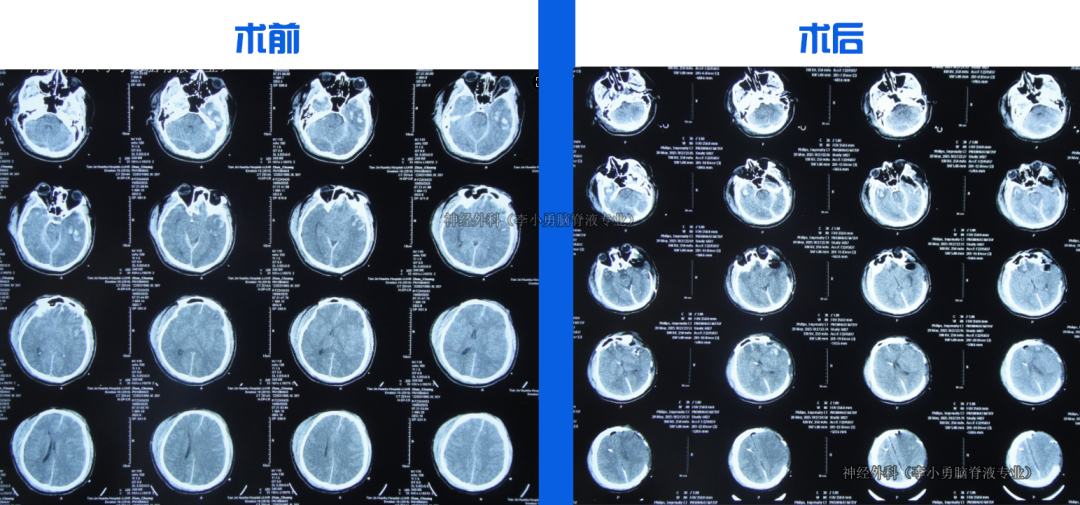

入院當天行腦室外引流術。治療18天后意識轉清,腦脊液由渾濁變清亮。第22天改為腦室腹壁外引流,持續(xù)引流、抗感染、控制顱內(nèi)壓力。第36天骨窗開始塌陷,提示顱內(nèi)壓力有效控制。住院1月零23天行顱骨修補術。

經(jīng)過持續(xù)引流和腦脊液凈化,患者在治療2月零6天時能下床走路,3月零2天拔除鼻飼管、走路變穩(wěn)。在腦脊液化驗持續(xù)達標后,于住院5月半時行腦室腹腔分流術。治療近5月余出院時:神志清楚,言語正常,走路基本正常,僅遺留右上肢活動稍差。出院后2月隨訪,右上肢功能進一步恢復。